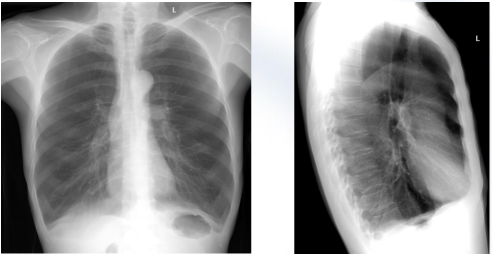

慢阻肺x线

胸部正位片:慢性阻塞性肺气肿,膈下可见游离气体.

病例读片-胸片